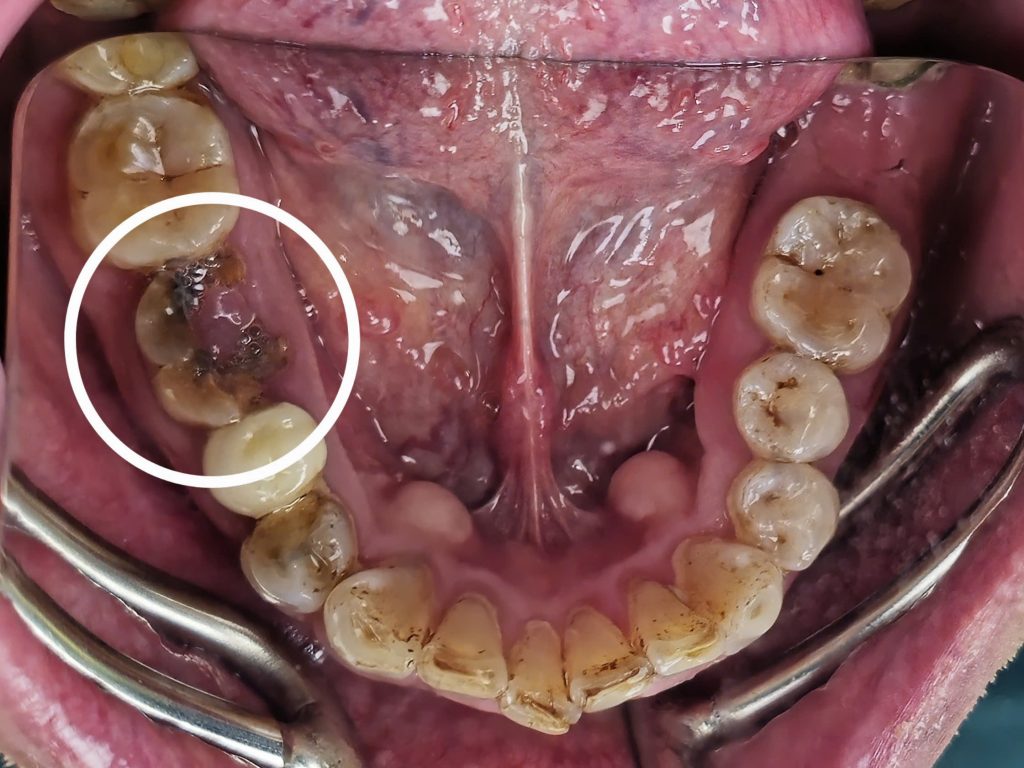

Cùng tìm hiểu quy trình cấy ghép Implant an toàn tại Nha Khoa Ace Smile qua trải nghiệm thực tế của anh Cường.

Bước 1 – Thăm Khám & Chụp XQ 3D